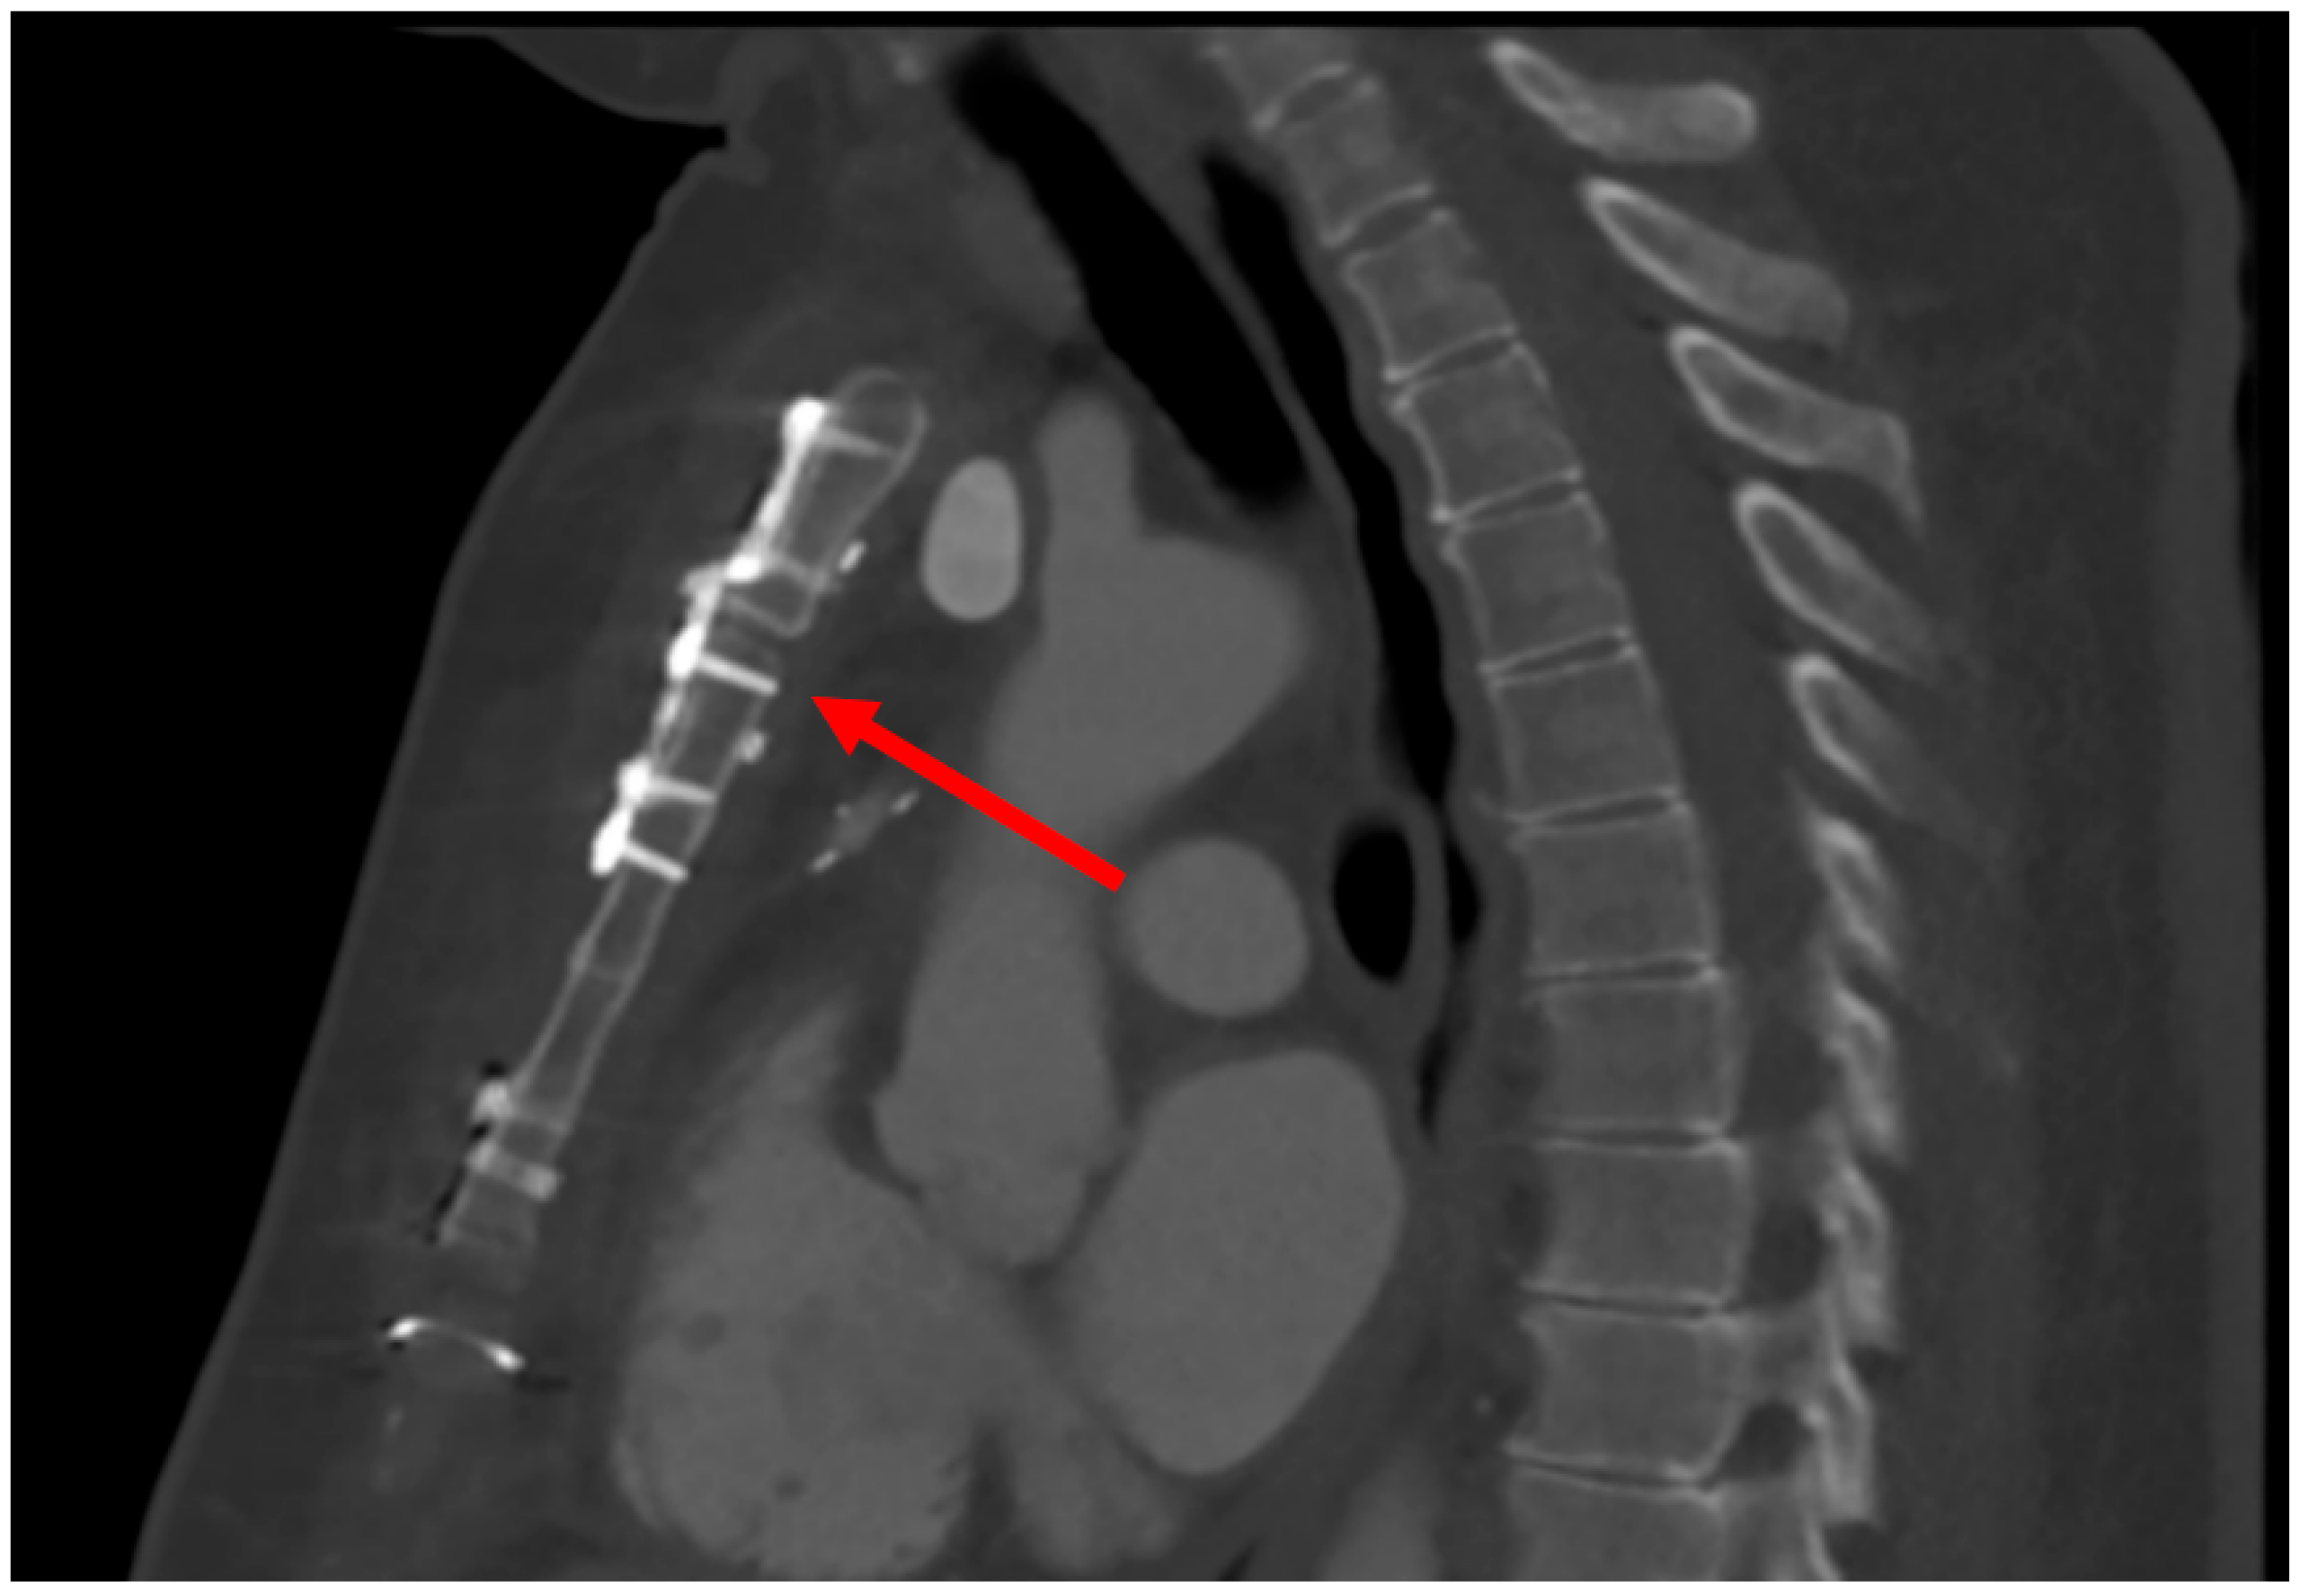

4.1.1. Case 1